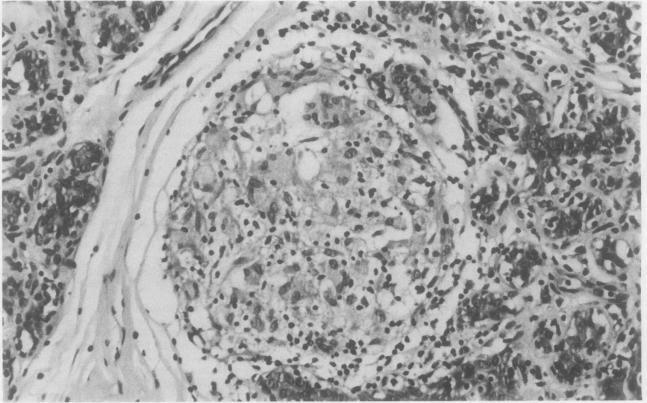

Sarcoid granulomata were found incidentally in the mammary lobules adjacent to an excised fibroadenoma in a case of sarcoidosis of the breast. The diagnosis of sarcoidosis was established by the radiological finding of bilateral hilar lymphadenopathy, raised concentrations of serum angiotensin converting enzyme and lysozyme, and, finally, by a positive Kveim test.